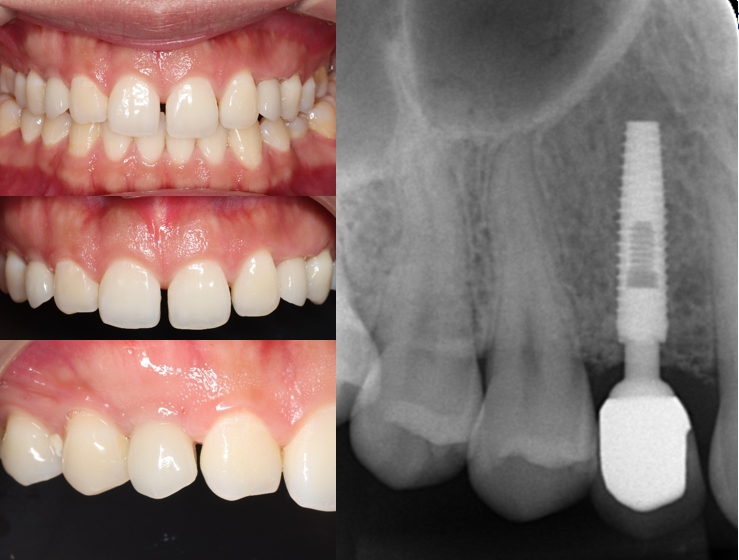

Guided placement of WEGO Sedga Φ3.0×12mm dental implant in site 13

Insertion torque: 28 N.cm

Three-month follow-up ISQ values: 71–73 (high stability)

Final restoration: Zirconia crown with excellent esthetic and functional results

Stable implant and healthy gingiva

Satisfactory esthetics and patient satisfaction

One-year follow-up: No complications, stable crestal bone level, no prosthetic loosening or tissue recession